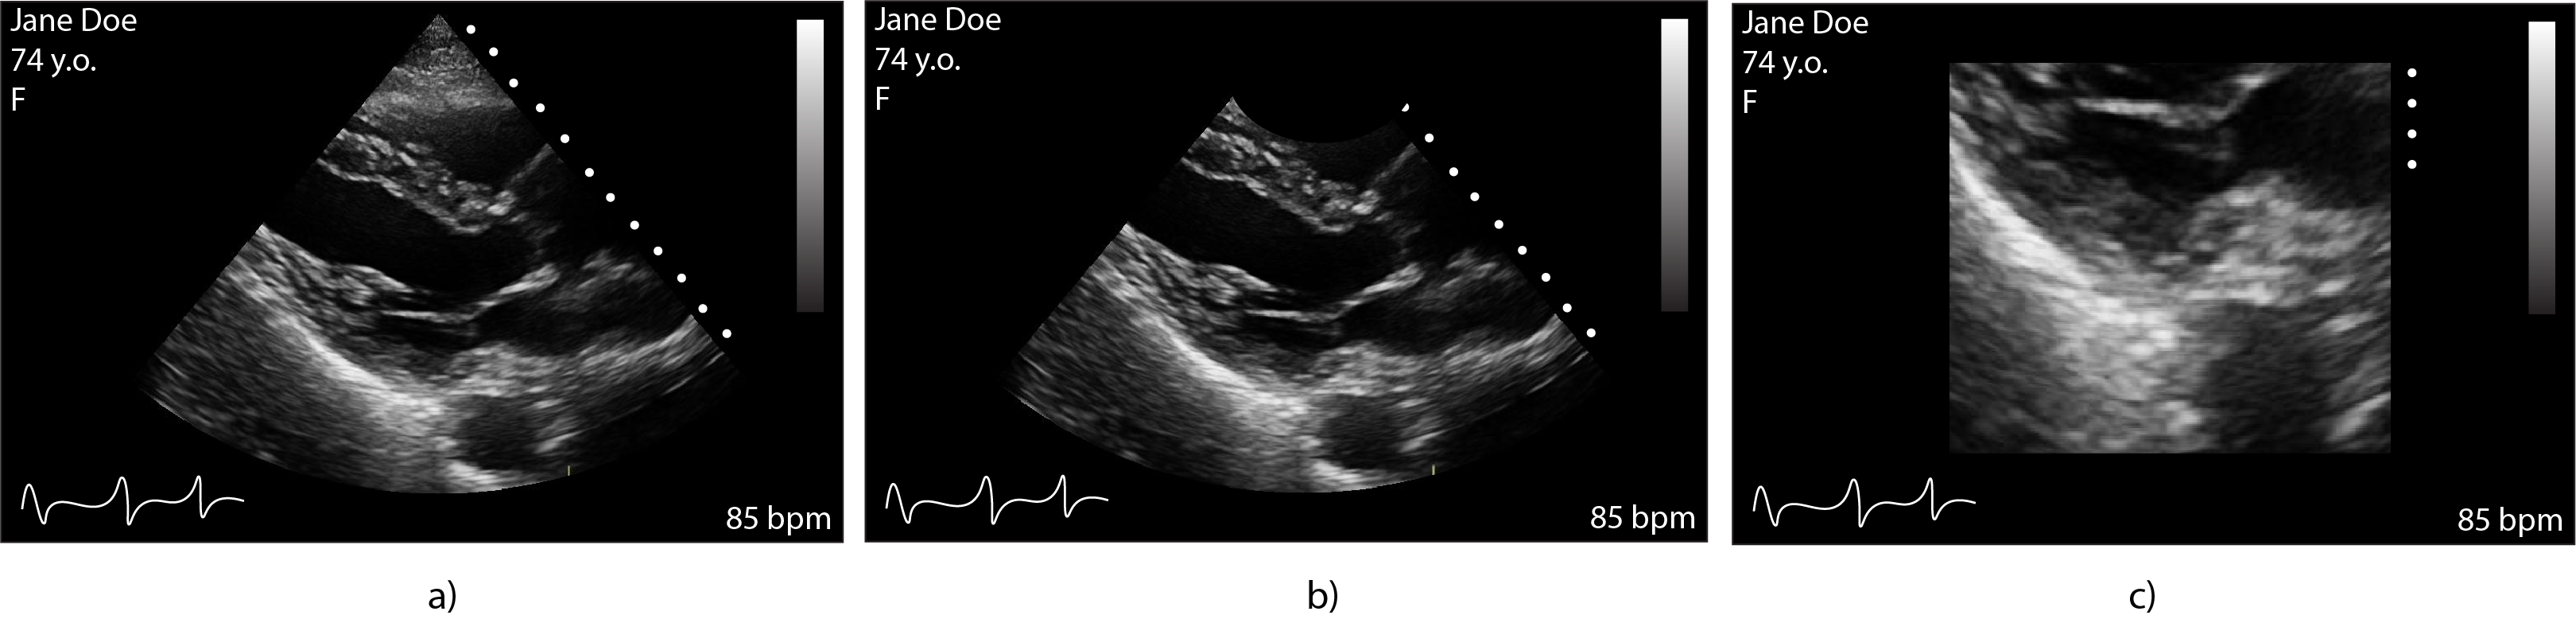

Ultrasound images typically resemble one of the three formats outlined in Figure 1. The shape differences are by-products of the manufacturing system and the ultrasound probe being used - phased array, curvilinear and linear in Figure 1a, 1b, and 1c, respectively [17]. Data were processed as DICOM formatted images; a typical format used in hospital-based PACS [9]. These typically contain metadata about the patient, study ID, the machine used to acquire the data, etc [18]. Reading these image volumes into Python 3 we can separate the metadata from the image arrays and process them as needed. Cardiac ultrasound (echocardiographic) images were acquired from the Northwestern University Echocardiography Core Laboratory (NUECL) repository, this study was approved by the institutional review board (STU00217900). All echocardiograms were done using an institutional review board-approved protocol, and all patients provided written informed consent. A Vivid T8 ultrasound system (GE Healthcare, Waukesha, WI) was used to perform all echocardiographic studies.

Refer to caption

Figure 1: Examples of the structure of a given ultrasound based on probe type. a) phased array, b) curvilinear and c) linear